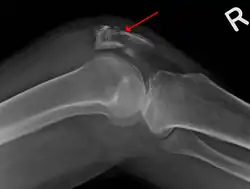

A fracture of the patella seen on a lateral view | |

Osteochondral fracture of patella